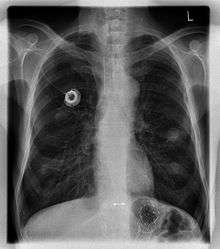

In medicine, a port is a small medical appliance that is installed beneath the skin. A catheter connects the port to a vein. Under the skin, the port has a septum through which drugs can be injected and blood samples can be drawn many times, usually with less discomfort for the patient than a more typical "needle stick".

The port is usually inserted in the upper chest (known as a "chest port"), just below the clavicle or collar bone, leaving the patient's hands free.

A port consists of a reservoir compartment (the portal) that has a silicone bubble for needle insertion (the septum), with an attached plastic tube (the catheter). The device is surgically inserted under the skin in the upper chest or in the arm and appears as a bump under the skin. It requires no special maintenance and is completely internal so swimming and bathing are not a problem. The catheter runs from the portal and is surgically inserted into a vein (usually the jugular vein or less optimally the subclavian vein. Ideally, the catheter terminates in the superior vena cava or the right atrium. This position allows infused agents to be spread throughout the body quickly and efficiently.